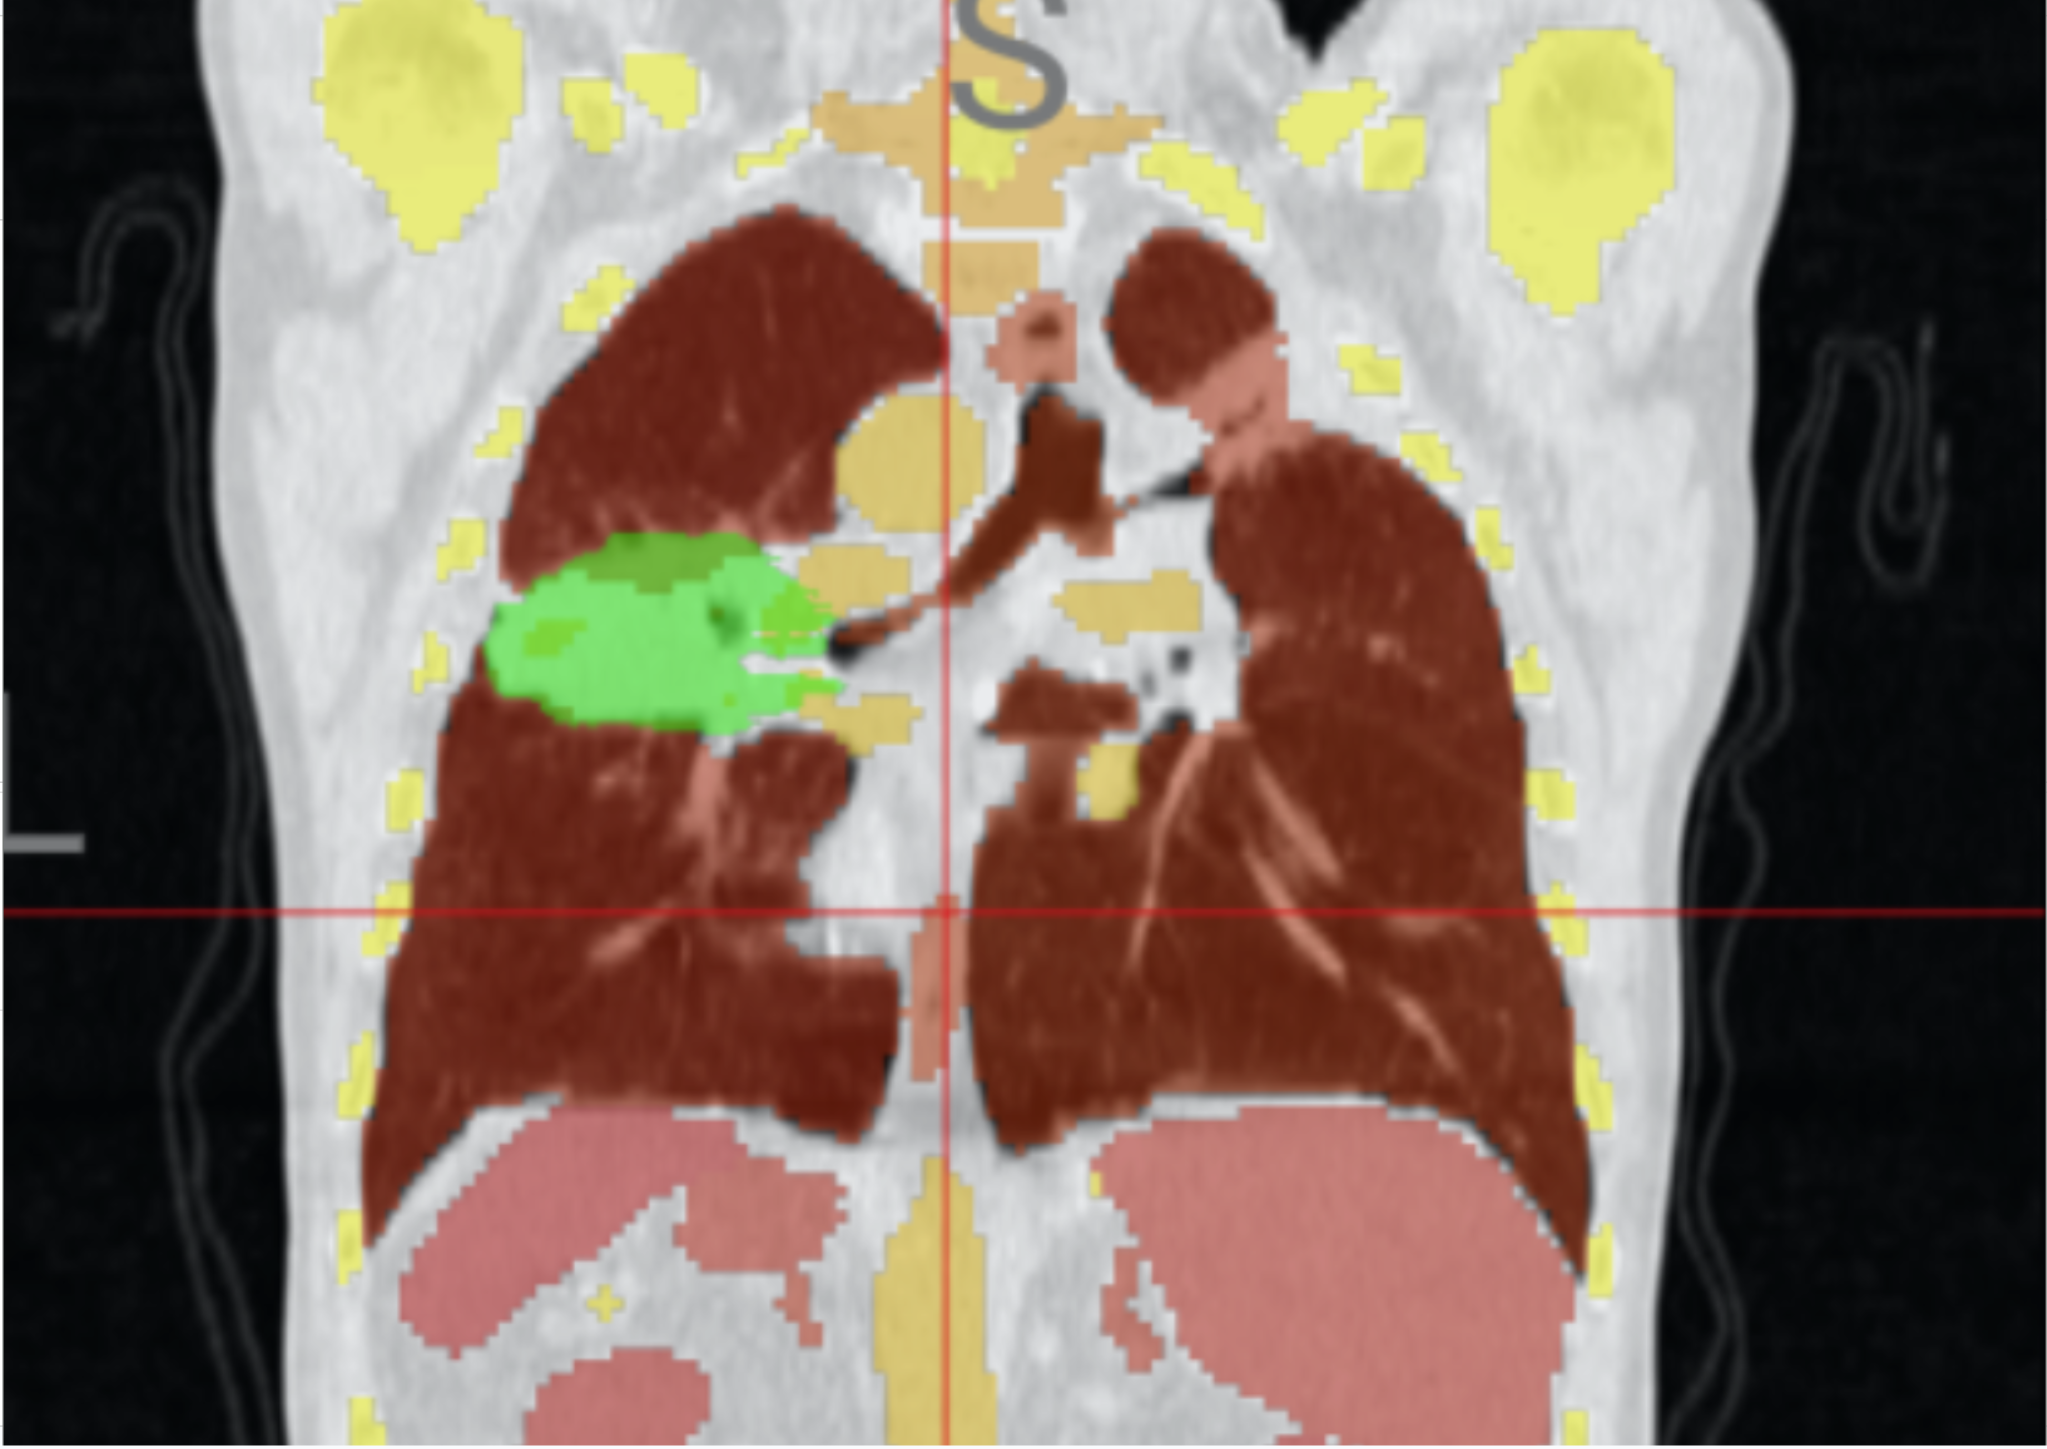

Enhancing Medical AI with Physiologically-Informed Data Augmentation

NeurIPS · submission in progress

Physiology-guided augmentation pipelines that explicitly model breathing motion and anatomical deformation to improve robustness of medical segmentation.